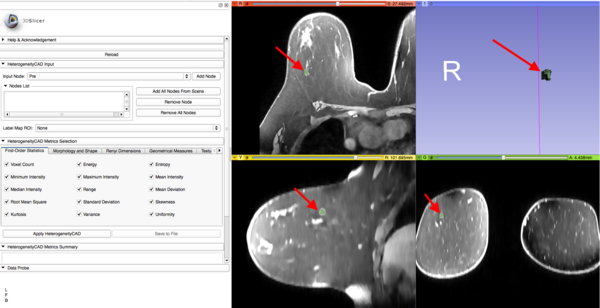

HeterogeneityCAD.PNG

The HeterogeneityCAD module is an image feature extraction toolbox primarily to quantify the heterogeneity of tumor images and their label maps. Source code for batch processing without the GUI is also included at the end of this document.

Navigating the Module

• HeterogeneityCAD Input

• Add Volume Node to the Nodes List

• Nodes can be either grayscale volumes or parameter maps (Volumes or Label Maps)

• Individual Nodes can be added be selecting a volume in the Drop-down menu and clicking 'Add Node'

• 'Add All Nodes from Scene' adds all volumes and labels in the scene

• Individual Nodes in the Nodes List can be removed by selecting them and clicking 'Remove Node'

• All Nodes in the Nodes List can be removed by clicking 'Remove All Nodes'

• A corresponding Label Map must also be selected to use as as the Region Of Interest (ROI)

• HeterogeneityCAD Metrics Selection

• Each tab menu corresponds to a list of metrics for a feature class (First-Order Statistics, Morphology and Shape, Renyi Dimensions...)

• An individual metric can be included or excluded from the computation by checking or unchecking its checkbox

• For some feature classes, unchecking the critical computations (in bold) will disable the other metrics

• Right-Clicking on a metric will open a description and a menu for editing metric parameters

• i.e. in the adjacent Figure right-clicking on the 'Mean Intensity' metric displays a description and a parameter menu